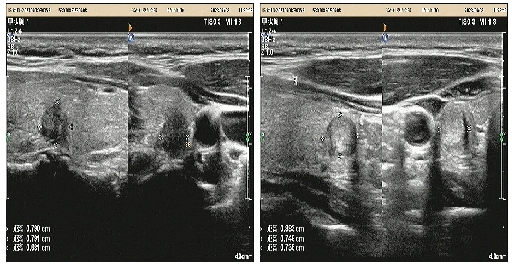

08、**女士,46岁

于2023年7月8日在邢台仁泰体检部体检,甲状腺彩超检查提示:甲状腺右叶可探及大小约0.9*0.7*0.7cm等回声结节,左叶可探及大小约0.8*0.7*0.8cm低回声结节,内可见多个点状强回声,边界清,形态欠规整,纵横比大于1。考虑:甲状腺结节伴钙化4b级。2023年7月8日首次回访,通知客户到三甲医院进一步检查。2023年7月14日跟踪回访,客户已在河北医科大学第二医院就诊,考虑甲状腺癌,准备手术治疗。